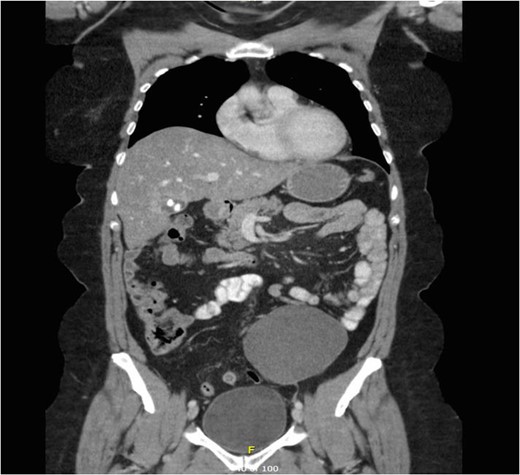

A mesenteric cyst is rare intra-abdominal pathology, with little literature to guide us on how to diagnose and manage it. We report the incident of a 57-year-old female who had an incidental finding of a sigmoid mesenteric cyst whilst undergoing an operation under the care of the Gynaecologists. A computed tomography scan and a flexible sigmoidoscopy followed to help diagnose the lesion as a cyst. A month later the 10 × 15 cm2 cyst was excised laparoscopically with no complications.

Mesenteric cysts are rare intra-abdominal lesions [1–4]. They occur in both adults and children with an incidence of 1/10 500–25 000 of adult surgical patients [5]. They are mostly found incidentally but patients with these cysts can sometimes present with non-specific complaints of abdominal pain and distension, or an abdominal mass [1]. They commonly originate in the small bowel mesentery, mesocolon (24%), retroperitoneum (14.5%) and very rarely from the sigmoid mesentery [6]. To diagnose these cysts, patients often require radiological investigations such as ultrasonography (USS), computed tomography (CT) and magnetic resonance imaging (MRI) [7]. Depending on their symptoms and location, these cysts can either be treated conservatively, or by open or laparoscopic surgical excision, and histological examination is often required to identify the origin of the cyst.

Investigations for sigmoid mesenteric cysts have previously included USS and CT [1, 7]; while in one case the symptoms were so severe that no radiological investigations were performed and the patient was taken to theatre for laparotomy for suspected appendicitis [8].